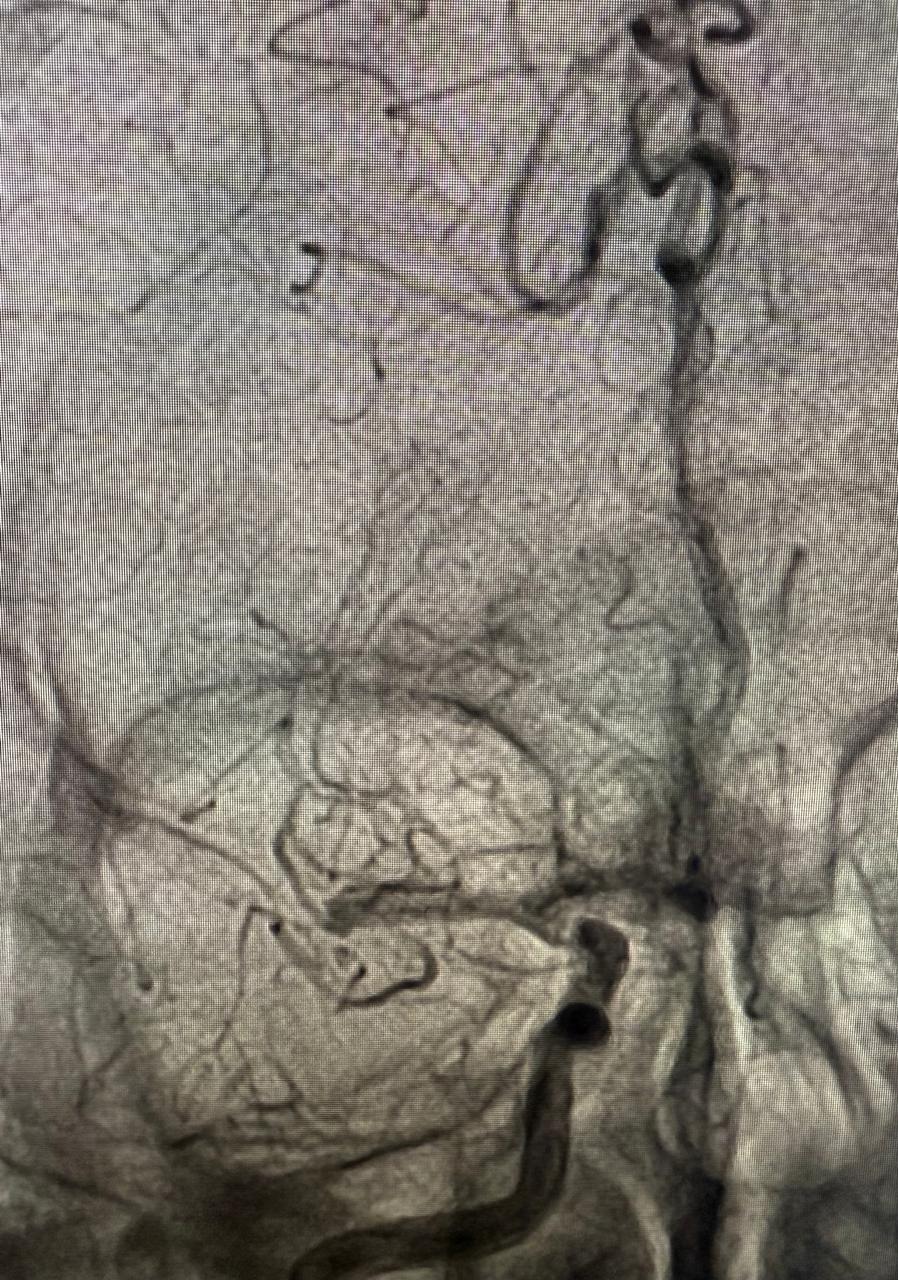

كما تم إجراء قسطرة مخية عاجلة لحالة أخرى لمريضة أربعينية محوّلة من مستشفى السنبلاوين، كانت تعاني من نزيف تحت الأم العنكبوتية، وتبيّن بالفحوصات وجود تمدد شرياني بالشريان الأمامي المتصل. وقد أجري التدخل العلاجي تحت إشراف الدكتور أحمد عفت، والدكتورة ندى عبد الحميد، وبما يتوافق مع أحدث البروتوكولات العلاجية المعتمدة.